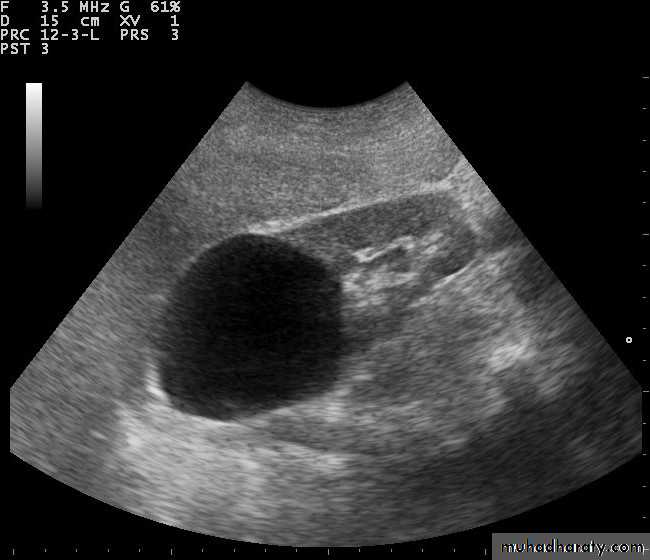

Polycystic renal disease in ultrasound demonstrate numerous cysts seen in cortex & medulla